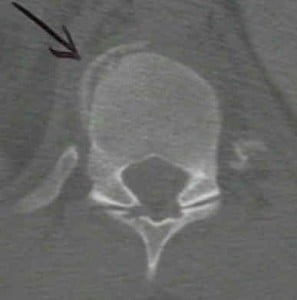

Some Radiographs

The following radiographs can give you and idea of what a chance fracture is and what is its location: